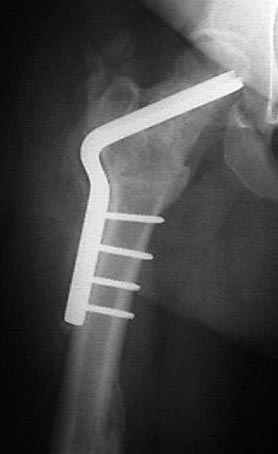

7:30 начало операции, больной на спине, попытка репозиции после анестезии N3, укладка больного на боку, доступ Kocher- Langenbeck, состояние седалищнего нерва около 2.5см кровоподтек, через joistick головка бедра приподнята, освобовождение сустава, фрагмент заднего края более 3х4 см репонирован на свое место. После промывания

сустава, репозиция вывиха (N4), фиксация фрагмента 2.7(4) мм шурупами и допольнительно реконструктивной пластиной на 8 дырок, фиксация 3.5мм шурупами проксимально и дистально.

Интраоперционные N5 косая запирательная и N6 подвздошный снимок

11:50 больной в послеоперационной, рентгенограмма N7, компьютерная томограмма в тот же день N8-10

На рисунке N1 предоперационный план лечения ложного сустава шейки бедра- линия ложного сустава, угол и направление введения импланта, клиновидная остеотомия в градусах и миллиметрах, второй снимок после коррекции, расчет, на сколько удлиняется конечность и размеры импланта;

N3 рисунок окончательный снимок, после операции моя рентгенограмма должен выглядеть примерно как эта картина. На N4 снимке клин перед удалением; N5 послеоперации 3 нед.; N6 окончательная рентгенограмма.

варус при проксимальном отделе 95 градусной пластиной.